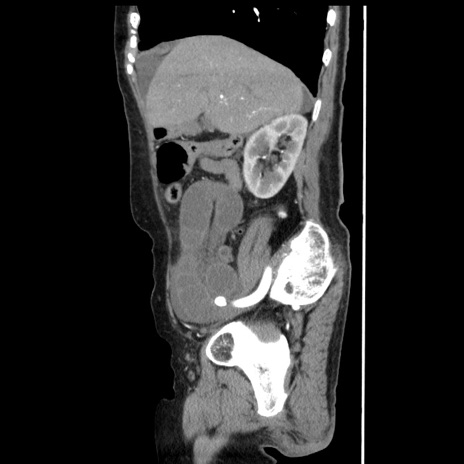

冠状断像

【症例】80歳代女性

【主訴】腹痛

【現病歴】8時間前から腹痛あり来院。

【既往歴】糖尿病、脂質異常症、子宮体癌にて子宮全摘術

【身体所見】意識清明・会話良好だが腹痛で苦悶様、全腹部にわたって反跳痛と圧痛あり

【データ】WBC 13600、CRP 0.14、LDH 224、CK 90